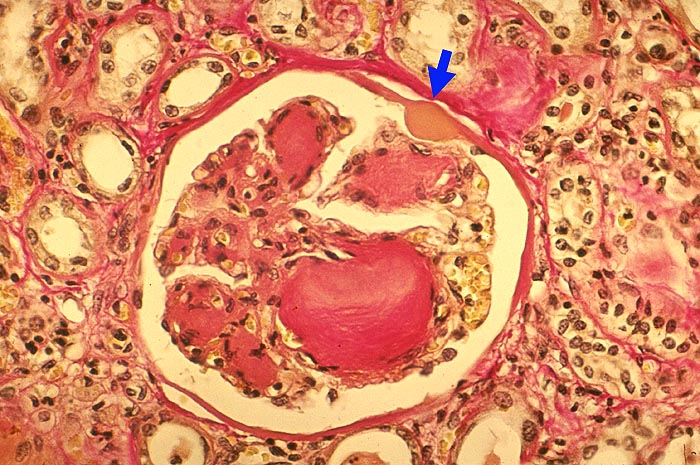

PathoPic – image database / PathoPic ID 1907 - Noduläre Glomerulosklerose Kimmelstiel-Wilson

Noduläre Glomerulosklerose Kimmelstiel-Wilson

Das Mesangium ist knotig verbreitert. Der grösste Knoten zeigt eine lamelläre Schichtung. Die Glomerulusschlingen über diesem Knoten sind teils leicht dilatiert. In der Bowman'Kapselbasalmembran ist ein Kapseltropfen erkennbar.

Noduläre Glomerulosklerose: Zwiebelschalenartig geschichtete, azelluläre Knoten im Mesangium. Primär leichte Hyperzellularität der Noduli. Im Allgemeinen folgt die noduläre Glomerulosklerose der diffusen Glomerulosklerose vor allem bei Typ I Diabetes. Dabei oft multiple kleine Knoten im Mesangium. Beim NIDDM gelegentlich einzelne sehr grosse Noduli mit nur wenigen Glomeruli ohne relevante diffuse Glomerulosklerose. Die noduläre Glomerulosklerose ist aber nicht einfach eine besonders schwere Form der diffusen, sondern wahrscheinlich eine unabhängige Erkrankung mit verschiedener Pathogenese.